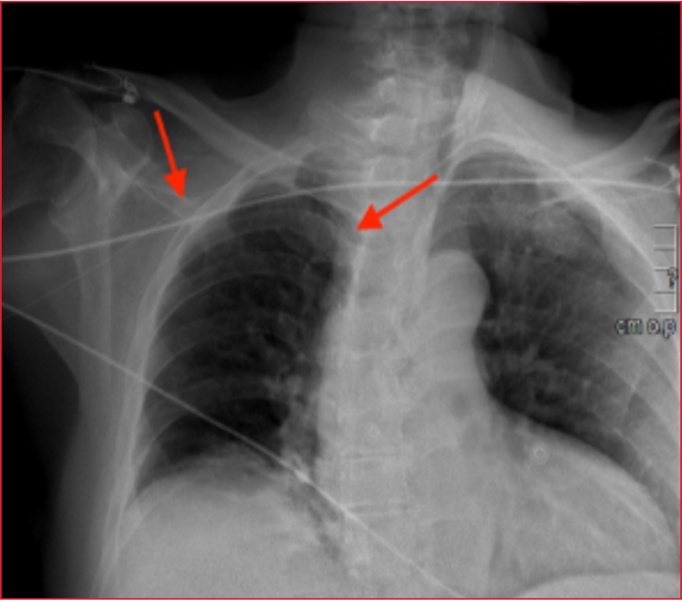

extraviada en el interior de la vena. Se tomó una radiografía de tórax en la

que se observó la guía metálica llegando hasta la vena cava superior (Figura

1).

Figura 1. Radiografía de tórax. Se observa la guía metálica a través de la vena subclavia derecha llegando a vena cava (flecha roja).